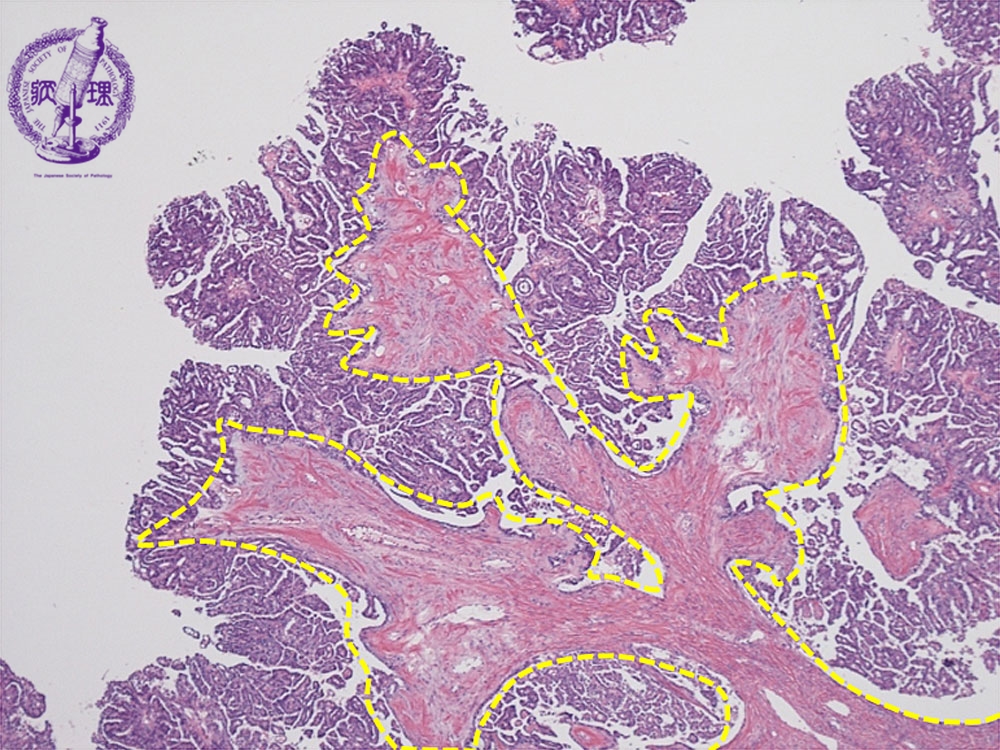

ミクロ像(HE弱拡大):卵巣漿液性嚢胞腺癌。比較的小型で立方状の癌細胞が線維性の間質(黄色点線)を伴いながら乳頭状に増殖している。

• ガイドあり